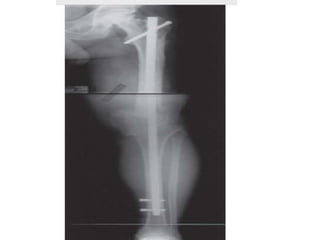

ARTHRODESIS WITH

INTRAMEDULLARY ROD FIXATION

Extensive bone loss does not allow compression

- after tumor resection

- failed total knee arthroplasty

• Advantages:

Immediate weight bearing

Easier Rehabilitation

Absence of pin track complications

High fusion rate

• Disadvantages:

-fat embolism

-intramedullary dissemination of infection

-potential impediment to obtaining correct alignment

- prolong duration of operation time

• Procedure :

periprosthetic TKA infection : 2-stage procedure is

recommended

Refreshing the distal femur and proximal tibia surfaces

IM nail is inserted in an anterograde fashion through the

piriformis fossa while the distal aspect of the nail should sit

close to the tibial plafond

Severe bony defects :

allograft and autograft bone grafts or a metal or polyethylene

spacer

• Post operative care:

Mobilized as soon as possible post operatively with assistive

device

Follow up 6 weekly

Radiological and clinical union : ambulatory aid dis continued